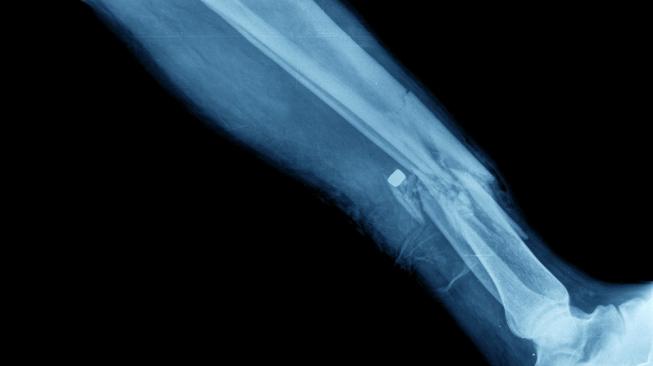

Disampaikan dr. Phedy, Sp.OT(K) anggota Sports, Shoulders & Spine Clinic di Siloam Hospitals Kebon Jeruk, sebenarnya kasus patah tulang tak selalu harus berakhir di meja operasi. Menurut dia, tulang merupakan organ tubuh yang unik karena mampu meregenerasi dengan sendirinya.

"Jadi tulang yang patah itu bisa nyambung sendirinya tanpa operasi. Peran operasi hanya memposisikannya pada posisi yang bagus sehingga tumbuhnya sempurna dan bisa menjalankan fungsinya dengan baik," ujar dr Phedy dalam temu media di Siloam Hospital Kebon Jeruk, Senin (21/1/2019).

"Ke dukun patah tulang bisa sembuh itu karena memang bisa dengan sendirinya tapi apakah posisinya benar? Kalau melengkung, pasien jalan jadi pincang. Tujuan operasi itu memperbaiki posisinya," imbuh dia.

Dr Phedy mengatakan bahwa masyarakat sebaiknya tidak perlu takut untuk memeriksakan ke dokter tulang jika mengalami keluhan pada tulang. Menurut dia 80-90 persen kasus orthopedi tidak perlu diselesaikan dengan operasi.